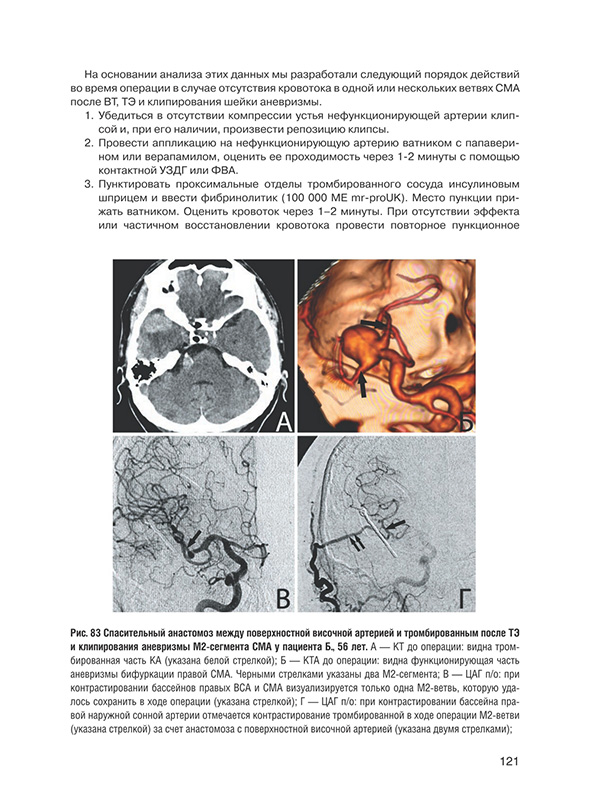

Анализ исходов у больных с интраоперационным тромбозом артерий